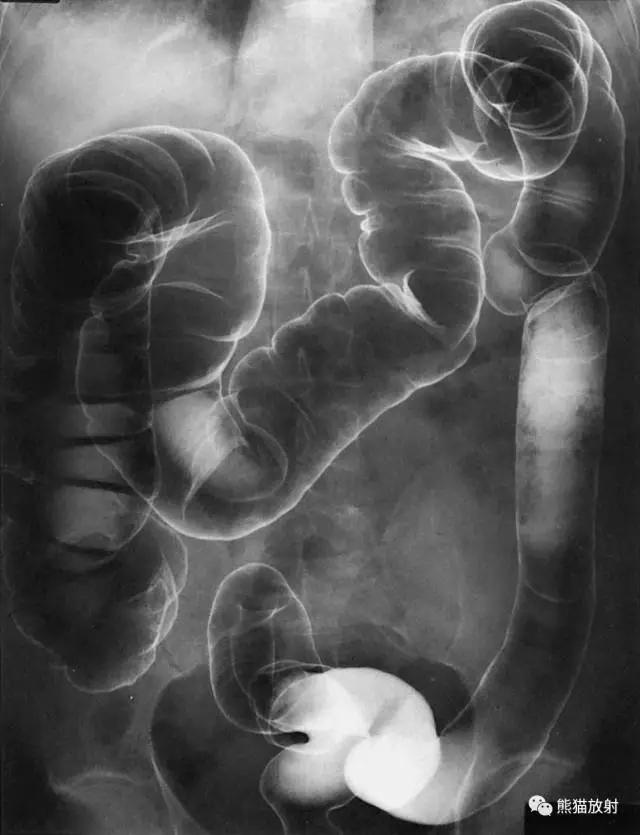

10 Colon 结肠

1 Splenic flexure of the colon 结肠脾曲,2 Hepatic flexure of the colon 结肠肝曲,3 Ascending colon 升结肠,4 Transverse colon 横结肠,5 Descending colon 降结肠,6 Haustra 结肠袋,7 Ileocecal valve 回盲瓣,8 Cecum 盲肠,9 Sigmoid colon 乙状结肠,10 Appendix 阑尾,11 Rectum 直肠